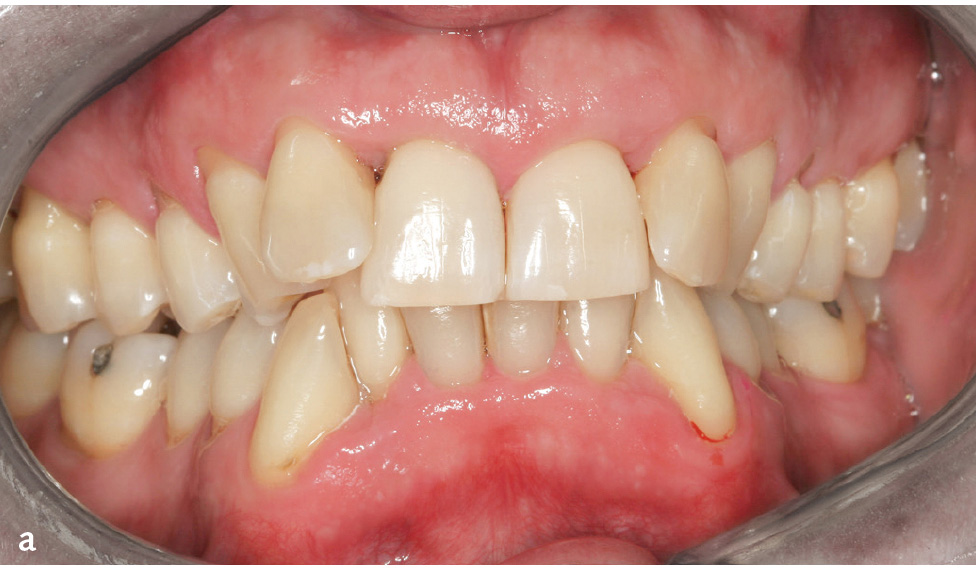

Abb. 1a bis d Parodontitis: a) Mann im Alter von 52 Jahren, Parodontitis, generalisiertes Stadium III, Grad C10: klinische Ansicht (Zahnfehlstellungen im Ober- und Unterkieferfrontzahnbereich, 31 Zahnstein); b) Röntgenstatus zu Abb. 1a: generalisierter überwiegend horizontaler Knochenabbau unterschiedlichen Ausmaßes (bis ins koronale Wurzeldrittel: 15–13, 23, 37–33, 43–47 [bis 33 % der Wurzellänge]; mittlere Wurzeldrittel: 17, 16, 12–22, 24–27, 32–42 [> 33 % der Wurzellänge]; auch am gleichen Zahn (z. B. 36); c) Frau im Alter von 24 Jahren: Parodontitis, generalisiert Stadium III, Grad C10; d) Panoramaschichtaufnahme zu Abb. 1c: Während sich an den Seitenzähnen des 2. Quadranten praktisch kein Knochenabbau findet, weisen andere Zähne Knochenabbau bis ins apikale Wurzeldrittel auf (z. B. 13, 33).